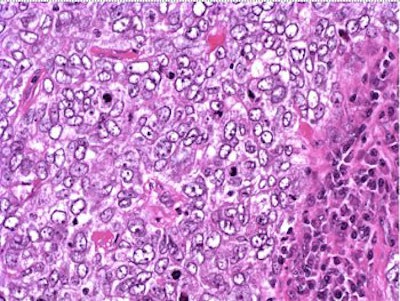

The patient underwent a lumpectomy with sentinel node biopsy. The pathology again showed extensive mitoses consistent with grade III invasive ductal carcinoma. Figure 4 (below) shows a representative microscopic section of the mass 4 cm from the nipple at a magnification factor of 100x. Figure 5 is the same area magnified 400x. Figure 6 shows a representative microscopic section from the other mass, which was 3 cm from the nipple magnified 100x. Figure 7 is magnified 400x. The tumors were estrogen receptor- and progesterone receptor-negative. Two sentinel nodes were negative.

Figure 6: Above, IDC right breast, 10 o'clock, 3 cm from the nipple magnified 100x. Figure 7: Below, IDC right breast, 10 o'clock, 3 cm from the nipple magnified 400x. |

![]() |